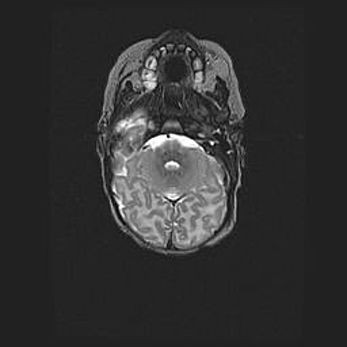

Аномалия Денди-Уокера. Признаки гипоплазии мозолистого тела.

Возраст: 5 месяцев 3 дня

Вес: 5550 г

Пол: мужской

Окружность головы: 39 см

Срок гестации: 40 недель

Аномалия Денди-Уокера – это порок развития головного мозга, для которого характерна триада симптомов: гипотрофия или аплазия червя мозжечка и/или полушарий мозжечка, расширение четвёртого желудочка с формированием ликворной кисты задней черепной ямки, гипертензионная гидроцефалия различной степени.

Гипоплазия мозолистого тела относится к дефектам внутриутробного этапа развития мозговой ткани, возникающим в процессе закладки структур головного мозга, что происходит на начальных этапах развития эмбриона.